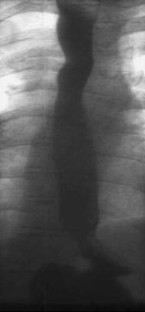

Fig. 3